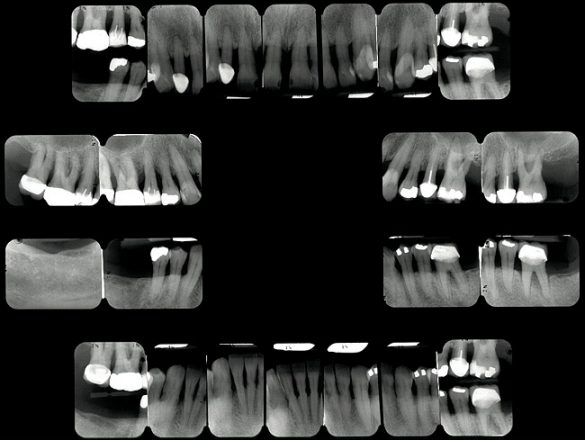

Examinarea a evidenţiat adâncimi de sondare generalizate cuprinse între 5-9mm, cu sângerare generalizată şi locaţii cu supuraţie. Combinaţia recesiunii cu adâncimile de sondare a generat o pierdere de ataşament generalizată cu valori între 8-12mm. Radiografiile au evidenţiat pierdere osoasă orizontală severă, defecte osoase verticale multiple şi aspectul unei posibile comunicări parodontale apicale. Aproximativ jumătate dintre dinţi prezentau mobilitate de clasa I, cu dinţii restanţi având o mobilitate de clasa a 2-a şi a 3-a. Toţi molarii manifestau cel puţin o invazie de furcaţie de gradul 1, cu multiple implicări de gradul 2 şi 3. Diagnosticul s-a stabilit a fi AAP tip IV, parodontită avansată.

La examinarea clinică, o serie de dinţi prezentau restaurări directe mici acceptabile. Dinţii de la 1.7. la 1.4., de la 1.2. la 2.6., 3.6. şi 4.5. prezentau fie restaurări directe voluminoase, fie coroane cu acoperire totală, cu un grad ridicat de compromitere structurală. Nu s-au identificat leziuni carioase active. Implicarea pulpară era vizibilă la nivelul molarului 3.6.

Pacientul a relatat o tendinţă ocazională de bruxism. Examinarea a evidenţiat sensibilitatea musculaturii masticatorii şi crepitaţii la nivelul ATM. Era prezentă atriţia minimă la toţi dinţii frontali. Dinţii frontali erau în contact, iar dinţii maxilari frontali era evazaţi şi mobili. Istoricul pacientului privind bruxismul, alături de crepitaţii şi sensibilitatea musculară a contribuit la diagnosticul disfuncţiei ocluzale.

La examinare s-au obiectivat: dinamică labială maxilară crescută, cu afişarea în repaus a 3-4mm din incisivi. La zâmbetul total, marginile gingivale libere nu erau vizibile, datorită recesiunii, dar 2-4mm din structura radiculară era vizibilă dincolo de joncţiunea smalţ-cement (CEJ) la toţi dinţii superiori. Festonul ţesutului moale era apropiat de normal, însă părea neatractiv datorită gradului mare de recesie şi a pierderii papilei. În regiunea frontală inferioară s-a remarcat asimetria orizontală (fig. 2).